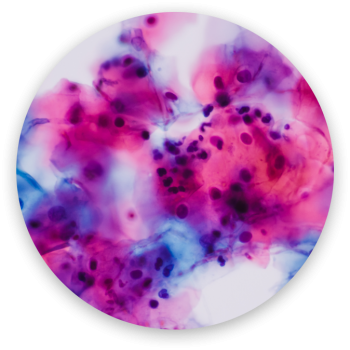

Candidiasis Crónica

La Candida Albicans es un hongo que habita normalmente en el aparato genital e intestinal de cada uno de nosotros sin crear ningún problema, pero en momentos de debilidad inmunitaria o fragilidad emocional puede proliferar de forma anómala. Esta proliferación Provoca síntomas como prurito, ardor, secreción blancuzca, hinchazón, dificultad en las relaciones sexuales y algunas veces, lesiones en los genitales externos.